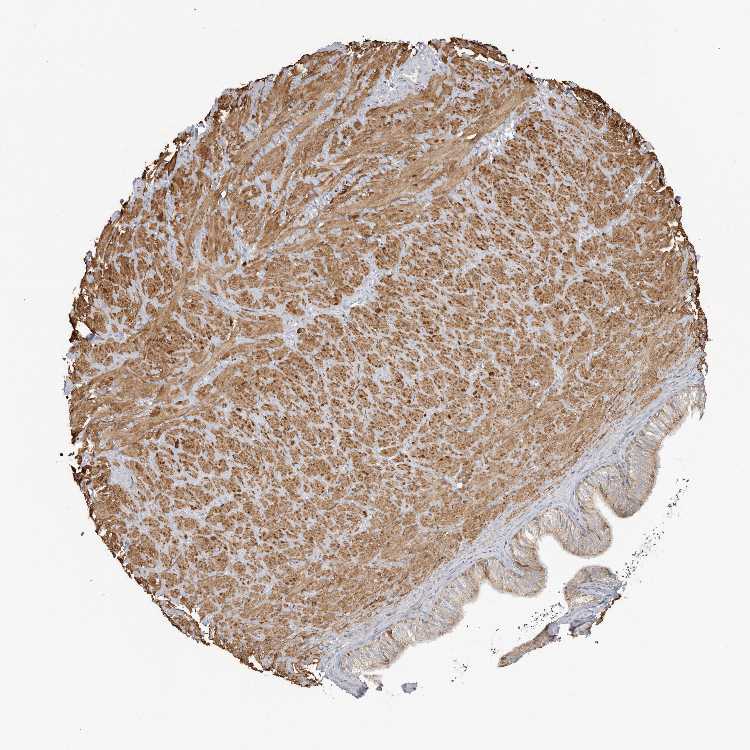

SOFT TISSUE 1 - Antibody stainingi

Antibody staining in the annotated cell types in the current human tissue is reported as not detected, low, medium, or high, based on conventional immunohistochemistry profiling in selected tissues. This score is based on the combination of the staining intensity and fraction of stained cells.

Each image is clickable and will lead to virtual microscopy that enables deeper exploration of all samples and also displays staining intensity scores, fraction scores and subcellular localization as well as patient and tissue information for each sample.

Antibody HPA023636Antibody HPA027962

Chondrocytes Low-

Fibroblasts Not detectedNot detected

Peripheral nerve -Low